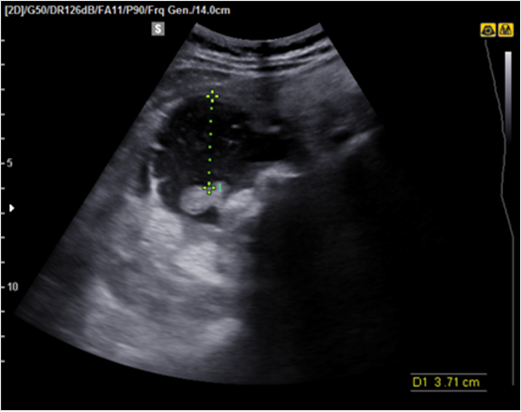

그림1. 자궁파열. 복강내 free fluid가 관찰됨

산전 및 산후 출혈의 진단에 있어 초음파의 역할을 매우 중요하다. 대표적인 산전 및 산후 출혈의 원인인 자궁파열, 태반조기박리, 자궁이완증, 잔류태반, 자궁내 동정맥기형의 진단과 치료에 있어서 초음파의 활용에 대해 알아본다.자궁파열자궁파열은 임상적으로 출혈, 복통, 저혈량성 쇼크가 있으면서 이전 자궁수술의 기왕력이 있을 경우 의심할 수 있다. 초음파에서 복강 내 액체처류(free fluid)가 보이거나, 자궁벽의 연속성이 사라지면서 무에코성 또는 저에코성 결손이 있고 그 사이로 혈종이 보일 경우 파열된 부분을 초음파로 확인할 수도 있다.

자궁파열의 위험요인으로는 이전 자궁수술의 기왕력이 가장 대표적이나, 지속적인 자궁수축이 있거나 자궁저부의 압박도 위험용인이 될 수 있으니 유도분만시 주의가 필요하다.